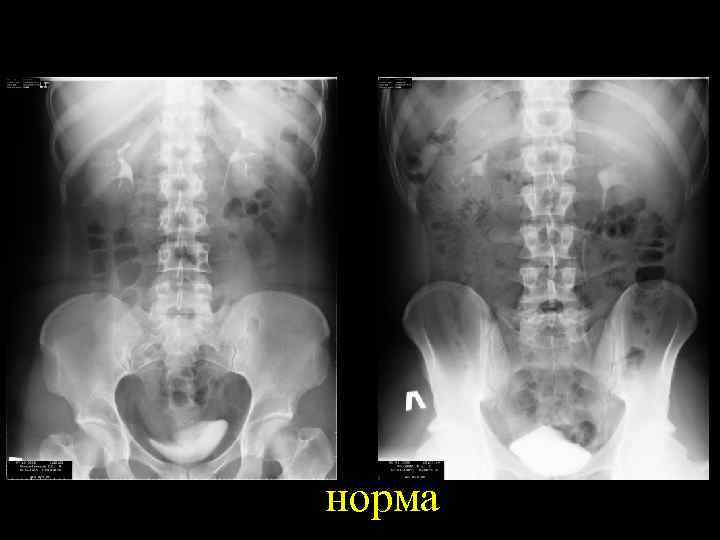

норма